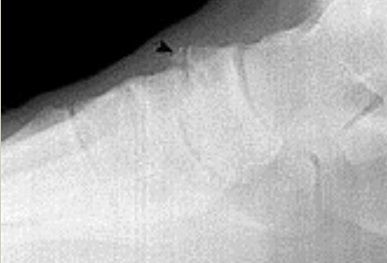

| Describe what the arrows are showing | Torus fracture of the 1st met. "Buckling" of the proximal one third diaphysis is seen both medially and laterally. Common in paediatric patients |